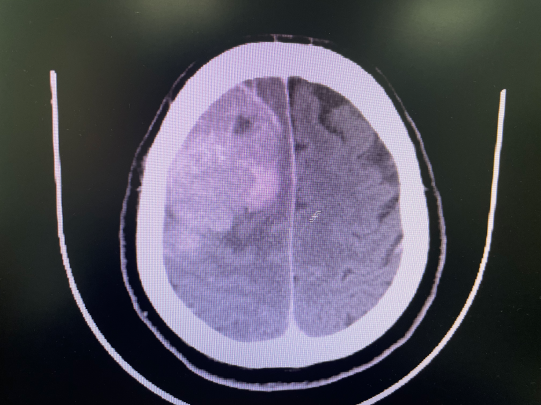

2023年3月,55歲的劉大叔因突發(fā)意識(shí)障礙3小時(shí)后被送往醫(yī)院。通過(guò)CT檢查,顯示為“顱內(nèi)占位性病變”。由于腫瘤大、位于功能區(qū),醫(yī)生建議轉(zhuǎn)至惠州市第三人民醫(yī)院神經(jīng)醫(yī)學(xué)中心神經(jīng)外科就醫(yī)。最終,劉大叔在家人的陪同下來(lái)到惠州三院進(jìn)行治療。

惠州三院神經(jīng)醫(yī)學(xué)中心神經(jīng)外科主任文世宏及其團(tuán)隊(duì)對(duì)患者病情進(jìn)行了全面的評(píng)估、討論,并為其制定了治療方案。結(jié)合病情,初步診斷為腦膜瘤。針對(duì)腫瘤的部位、刀口位置、大小及術(shù)后可能出現(xiàn)的并發(fā)癥等問(wèn)題,文主任及其團(tuán)隊(duì)進(jìn)行了詳細(xì)討論,最終確定了在顯微鏡下切除腫瘤的方案。